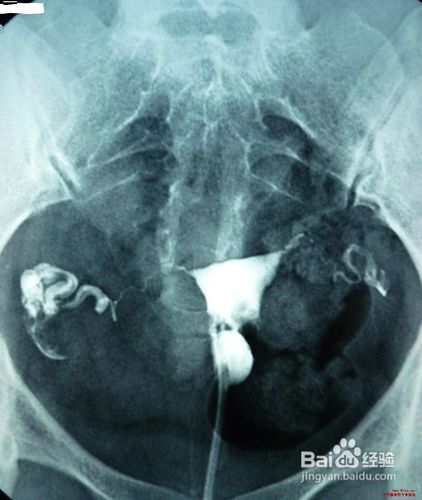

(2)子宫输卵管造影或者宫腔镜了解宫腔形态。